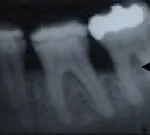

Periodontal Regeneration Case Studies Performed by Dr. Orth

Case 1: Before and after Periodontal Regeneration